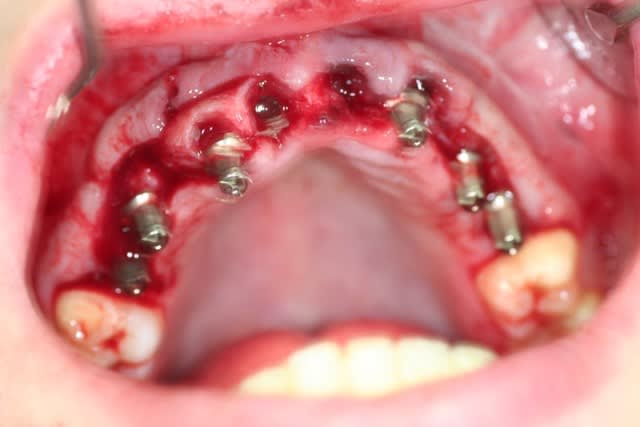

ok. traitement accepté par le patient.

finalement, j'ai décidé d'extraire les quatre incisives.

j'ai fait le pari de pouvoir mettre 6 direct abutments sur les implants pour faire un bridge scellé. ouf.....

désolé pour la qualité de l'image: nous n'étions que deux, et donc pas très simple....

la suite au fur et à mesure....

Piliers rzuz6r - Eugenol